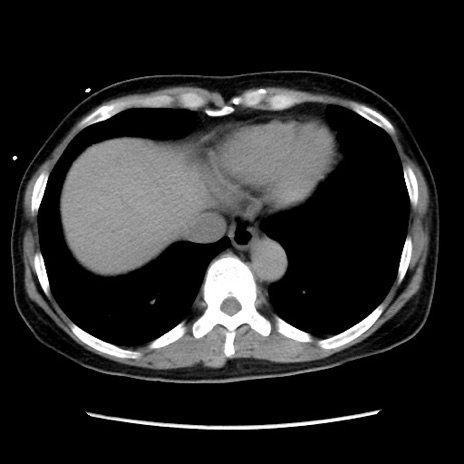

症例10(横断像)

【症例】 50歳代女性

【主訴】 腹痛

【現病歴】前日生レバーを食べた。今朝に排便あり。 昼前に突然発症の腹痛を生じ、当院救急外来を受診した。

【既往歴】 子宮筋腫にてで子宮全摘後

【身体所見】 意識清明、腹部:平坦、軟、下腹部やや左を中心に圧痛・反跳痛あり、筋性防御あり

【データ】WBC 7800、CRP 0.07